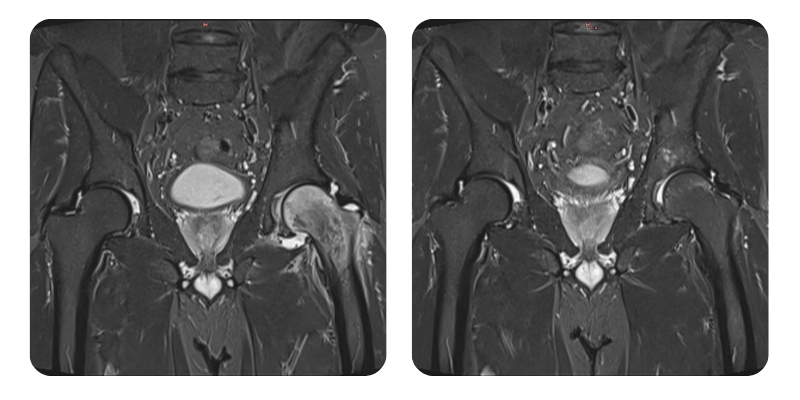

Înainte

După

J.A.V., 43 de ani - Edem cap femural stânga

Diagnostic: Edem cap femural stânga.

Se constată o reducere a edemului de peste 90% corelat cu clinica și se consideră vindecat.